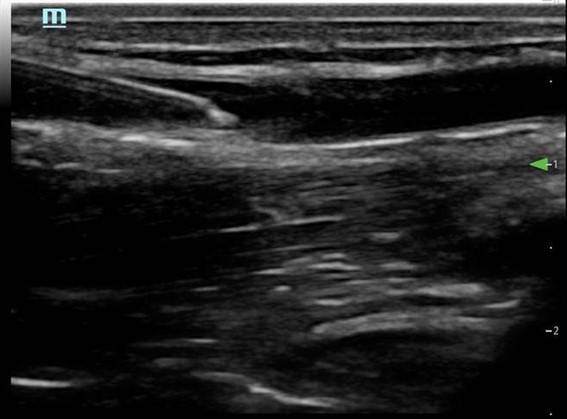

- Needle advances in the vessel (Fig. 7)

- Needle should be followed into the lumen of the vessel

- Sufficient catheter (1-2cm) should be seen in the vessel3 (Fig. 8)

Figure 7. Long axis approach: entering the vessel

Figure 8. Long axis approach: needle and catheter in vessel